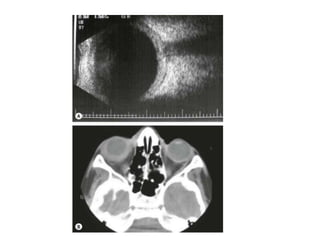

Ultrasound :

• Increased scleral thickness, scleral nodules and

separation of Tenon capsule from the sclera.

• Fluid in Tenon's space gives rise to the

characteristic ‘T’ sign in which the stem of the T is

formed by the optic nerve on its side and the cross

bar by the gap containing fluid

• Disc oedema, choroidal folds or retinal

detachment.

MR and CT may show scleral thickening and proptosis